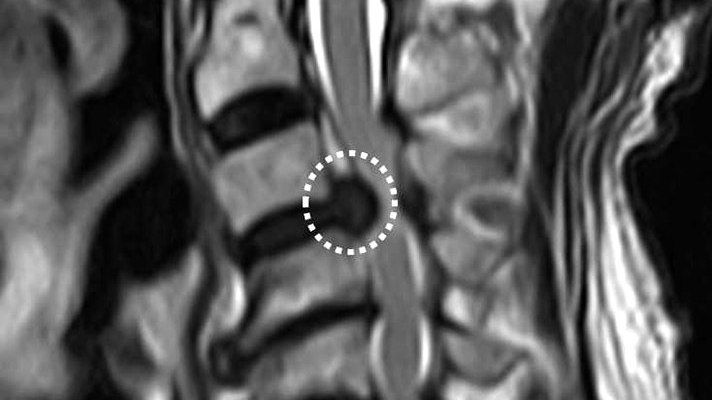

整形外科医今泉佳宣氏皆さんはモートン病という病気をご存じでしょうか。1876年にトーマス・モートン医師によって初めて報告された疾患です。足の裏の主に3番目と4番目の指(足趾(そくし))の間の付け...